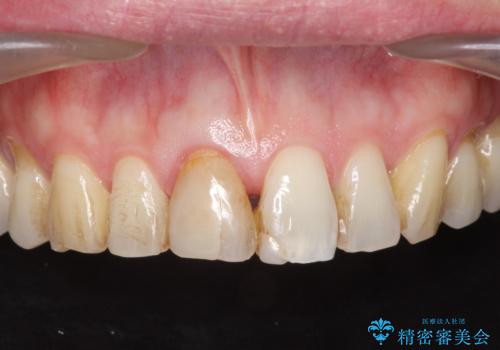

- 目立つ前歯の変色の改善を希望され来院されました。

根管治療を行いそのままにしていると歯は、徐々に変色を来します。

感染の疑われる根管内に対し再度根管治療を行い、セラミッククラウンを作製することで審美性の回復します。